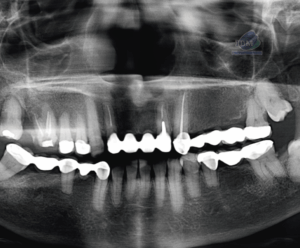

Paciente femenino de 53 años acude para una evaluación general. A la evaluación de la tomografía volumétrica (cone beam) bimaxilar en los cortes axiales (Figura 1) y tangenciales (Figura 2) se observa que adicional al foramen entoneano de lado derecho la presencia de dos forámenes accesorios de menor calibre uno mas hacia medial y el otro hacia caudal.

CORTES AXIALES